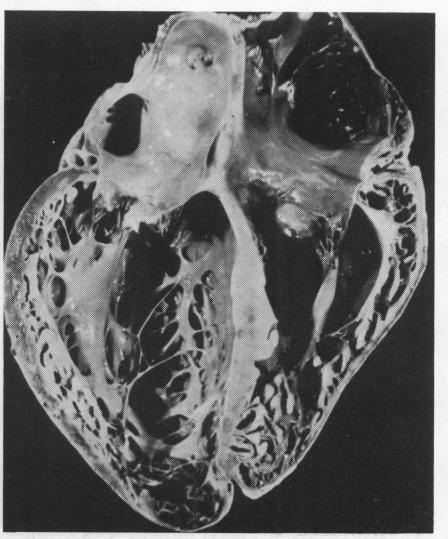

A retrospective study of Chagas's heart disease was carried out by a review of necropsy reports with special reference to the lesion known as the apical aneurysm. It was concluded that this lesion was more frequent in men, was unrelated to age, and was unrelated to heart weight. Patients dying of the cardiac consequences of Chagas's cardiomyopathy were more likely to have an apical aneurysm than those whose death was unrelated to the disease but the mode of death (sudden, or with heart failure) was unconnected with its presence. Transillumination from within the ventricle at necropsy was not only useful in demonstrating the aneurysm but also showed areas of myocardial thinning elsewhere. Thrombosis within the lesion was frequent. The aetiology of the apical aneurysm is discussed and it is concluded that while ischaemia, inflammation, thrombosis, and mechanical factors may produce and localise this lesion, the underlying cause is the basic pathogenetic process-parasympathetic nerve cell destruction.

通过回顾尸检报告,对恰加斯心脏病进行了一项回顾性研究,特别关注了被称为心尖动脉瘤的病变。研究得出结论,该病变在男性中更为常见,与年龄无关,也与心脏重量无关。死于恰加斯心肌病心脏后果的患者比那些死亡与该疾病无关的患者更有可能患有心尖动脉瘤,但死亡方式(猝死或心力衰竭)与心尖动脉瘤的存在无关。尸检时从心室内进行透照不仅有助于显示动脉瘤,还能显示其他部位的心肌变薄区域。病变内血栓形成很常见。文中讨论了心尖动脉瘤的病因,得出的结论是,虽然缺血、炎症、血栓形成和机械因素可能导致并定位该病变,但根本原因是基本的发病过程——副交感神经细胞破坏。